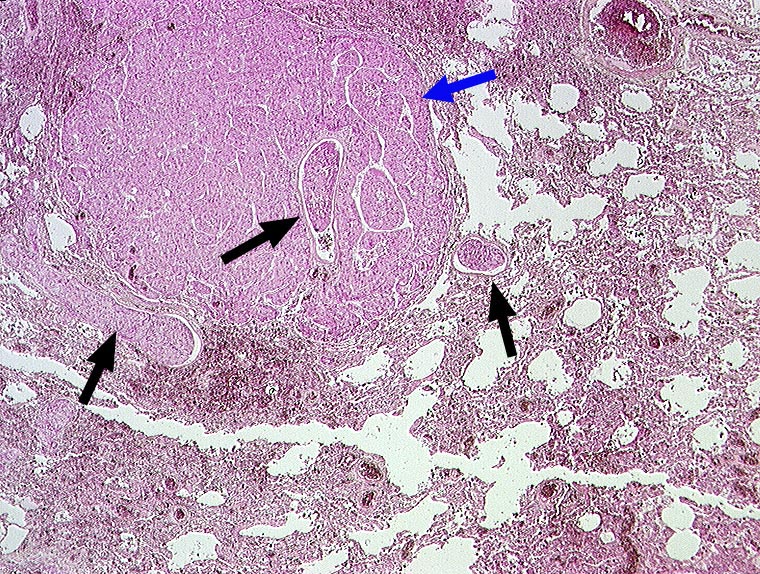

AP/ Hepatozelluläres Karzinom: Lungenmetastasen

Hepatozelluläres Karzinom: Lungenmetastasen

Lunge, Mediastinum mit Thymus

Lunge